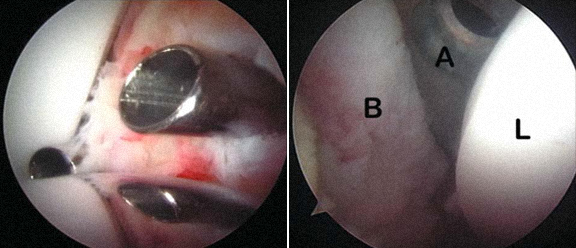

4 - Quisto intra-articular - exérese